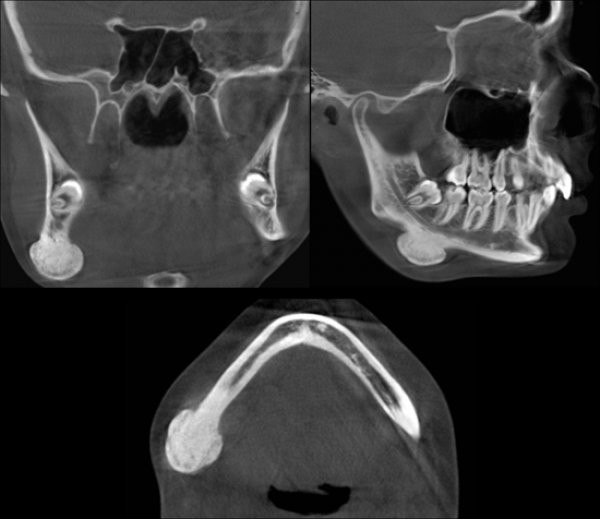

Osteoma Periférico en Mandíbula Dento Metric Radiología Dental Osteoma Dental Tratamiento Habitualmente el diagnóstico de los osteomas se realiza mediante una historia clínica completa, una. Our reviews here as well as previous case reports support that osteoid osteoma and osteoblastoma can and should be distinguished from one. It is prevalent at younger age but maximum seen in. Once your doctor diagnoses a benign osteoma, they’ll discuss the best osteoma treatment options. Osteoma Dental Tratamiento.

Osteoma Periférico en Mandíbula Dento Metric Radiología Dental Osteoma Dental Tratamiento Habitualmente el diagnóstico de los osteomas se realiza mediante una historia clínica completa, una. Conventional radiological examinations (dental panoramic tomography and water’ s view) are generally sufficient to diagnose an osteoma. Our reviews here as well as previous case reports support that osteoid osteoma and osteoblastoma can and should be distinguished from one. Once your doctor diagnoses a benign osteoma,. Osteoma Dental Tratamiento.